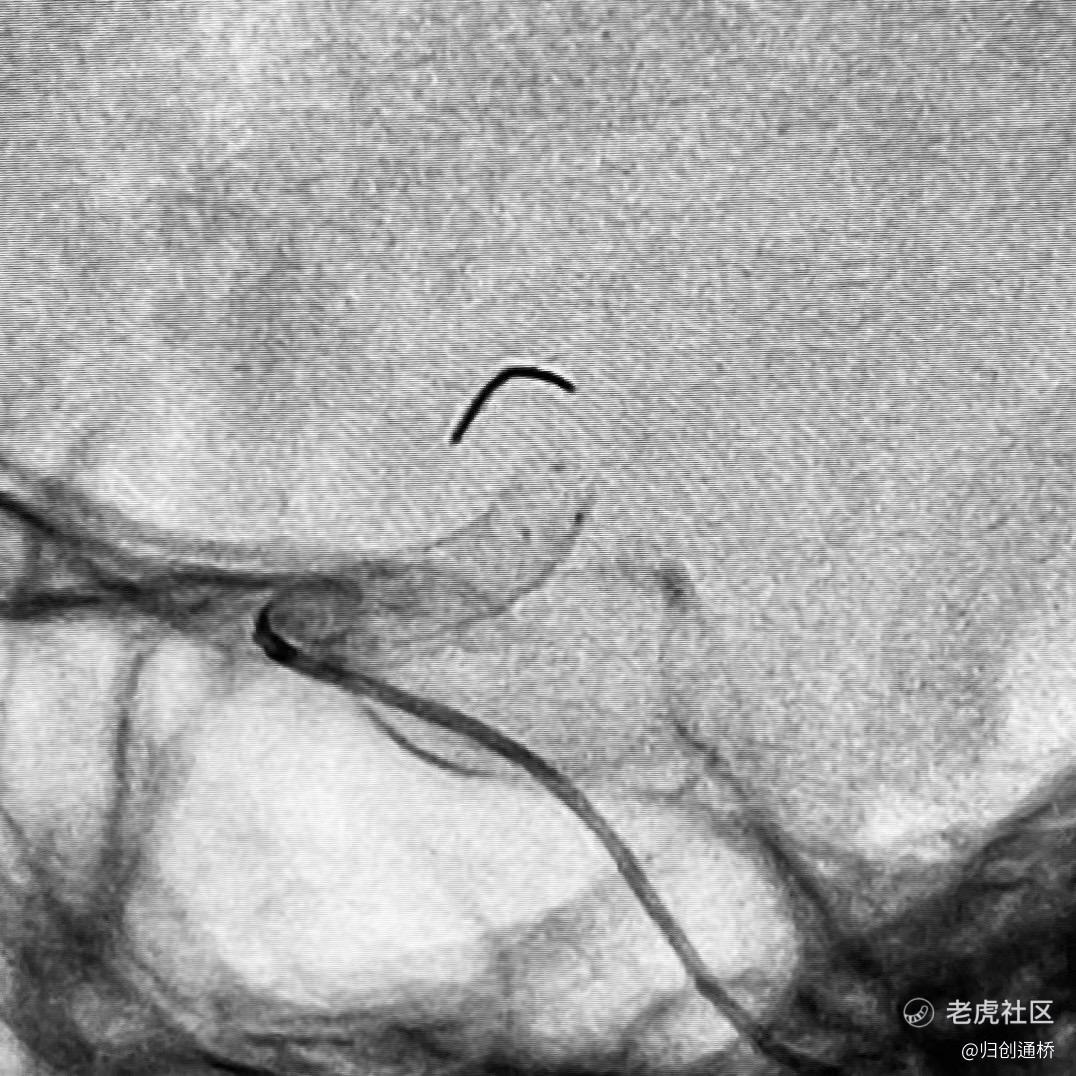

本次首例病人入组由长海医院洪波教授完成,入组病人颈内动脉较迂曲,动脉瘤位于眼动脉段,此次手术有一定挑战性。术后,洪波教授对于产品非常认可,他表示:“‘通桥麒麟’血流导向装置性能良好,推送过程非常顺利,释放后贴壁性判断良好,显影性明显,动脉瘤造影剂滞留,载瘤动脉通畅,手术过程顺利。希望病人能够预后良好,早日恢复健康。”